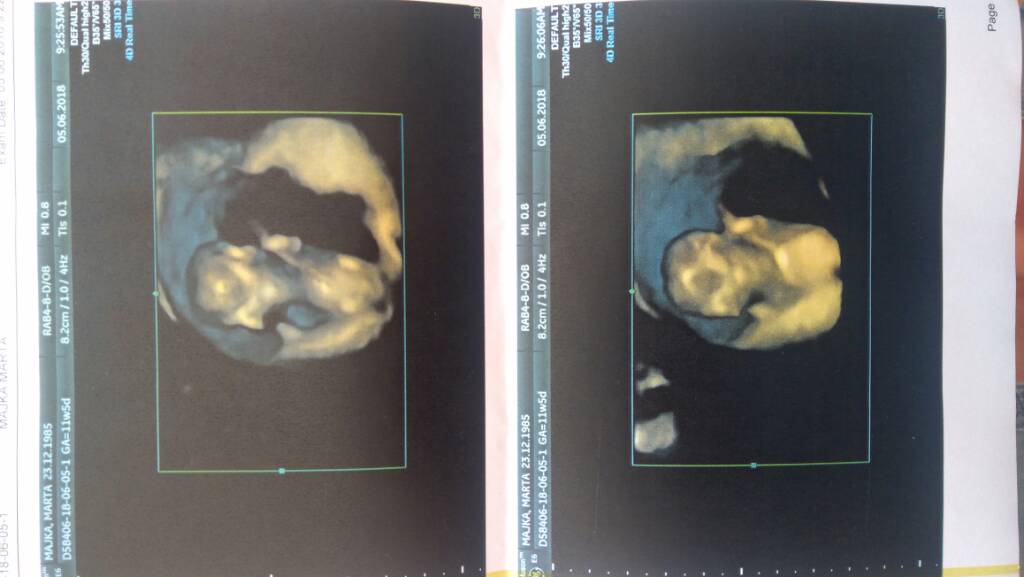

Hej Kochane przepraszam że nie odzywalam się ale taki jakiś dziwny czas, a więc tak 5.06 mieliśmy prenatalne Nasz Cud zdrowy miał 5,5 cm a po dzisiejszej wizycie u prowadzącego już 6 cm dr od prenatalnych stwierdził że oscylowalby w stronę dziewczynki ale narazie nic nie mówi powie na polowkoeych na początku sierpnia zaś 7.07 w dzień urodzin Mojej Mamy mamy kolejną wizytę